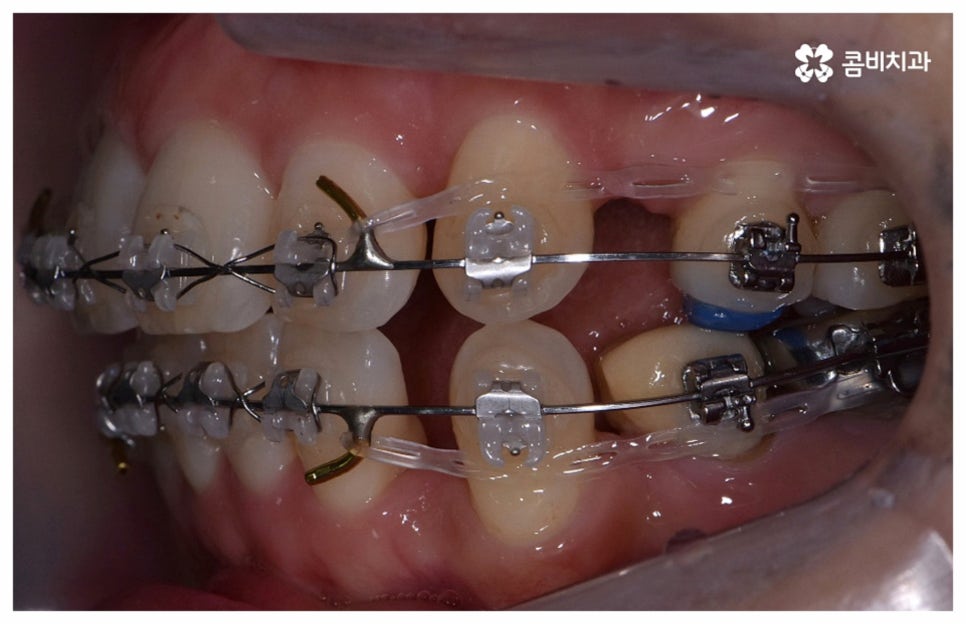

나이가 들어가면서 치아와 주위 조직들이 약해질 수 있고 치주 질환이 발생할 위험도 높아지기 때문에 중년치아교정 치료시 환자분들의 상황에 따른 맞춤 진료를 더욱 세심하게 진행할 필요가 있어요. 교정 방법이나 주의점에 대해서 꼼꼼하게 확인하고 계획을 세워야 할 뿐 아니라 교정 치료 전에 충치나 잇몸병과 같은 구강 질환이 발견되었다면 이를 미리 깨끗하게 치료하고 진행 과정 중간에도 장치에 음식물 찌꺼기가 끼지 않도록 위생 관리를 철저하게 해주며 치료 후 치아와 잇몸이 약해지지 않도록 환자분들 각각의 치아 이동 속도에 따라 무리하지 않는 것이 중요한 포인트라고 할 수 있습니다.

검진 후 부분 교정이 가능하지 않은 케이스라고 해도 요즘은 심미적인 교정 장치가 많이 나와 있으며 장치 자체로 인해 결과에 미치는 영향이 크지 않기 때문에 자신의 상황에 맞는 장치를 직접 선택할 수 있으니 의료진과 충분히 상담을 해 보시면 도움 받아 보실 수 있을 거예요. 특히 치아 색상의 브라켓을 이용한 세라믹 장치들이 심미성이 뛰어난데, 그 중에서도 자가결찰방식을 이용한 클리피씨 교정 장치를 이용하면 눈에 크게 띄지 않을 뿐 아니라 보다 적은 힘으로 부드럽고 지속적인 치아 이동을 가능하게 하기 때문에 통증도 줄이고 전체 교정 기간 역시 단축시킬 수 있다는 장점이 있으니 이에 대해서도 자세하게 알아보시길 바라고 있습니다.

위 사진은 환자분의 동의를 받아 이해를 돕기 위한

사진이며, 실제 치료 결과는 다를 수 있습니다.